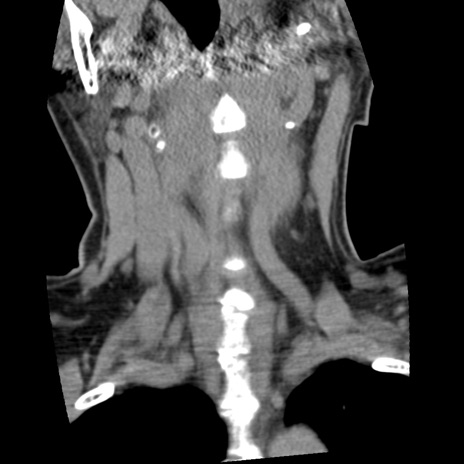

症例50 頚椎CT(冠状断像)

【症例】60歳代女性

【主訴】後頭部〜右後頸部にかけての痛み

【現病歴】本日飲食店でコーヒーを飲んでいたところ、突然後頭部〜右後頸部にかけて痛みが出現し、右上肢の感覚障害を伴ったため救急要請。

【身体所見】脳神経学的に明らかな異常所見を認めず。右上肢に軽度の感覚障害あり。

異常所見と診断は?

頚椎CT